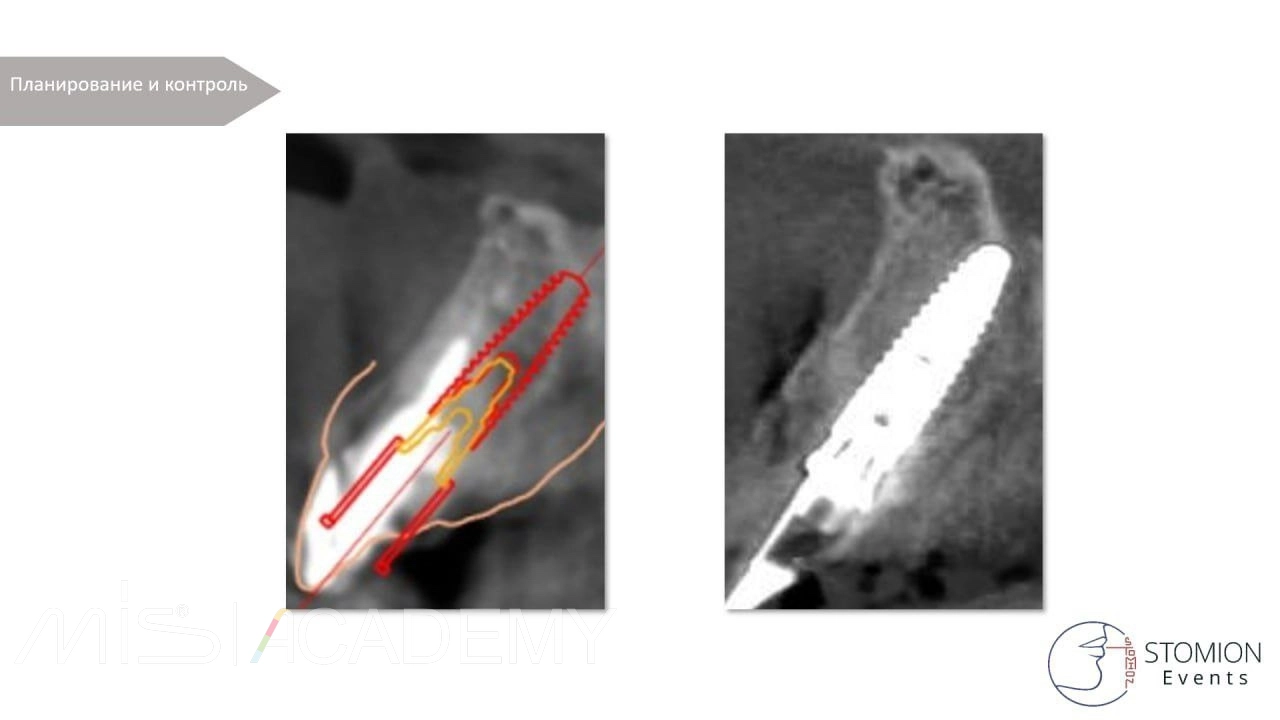

Атравматичное удаление зуба 1.1 с использованием системы Benex. Тип лунки — I (интактная).

— Выполнена одномоментная установка имплантата MIS C1 3,75 × 13 мм с коннектом 3 мм. Зазор более 2 мм.